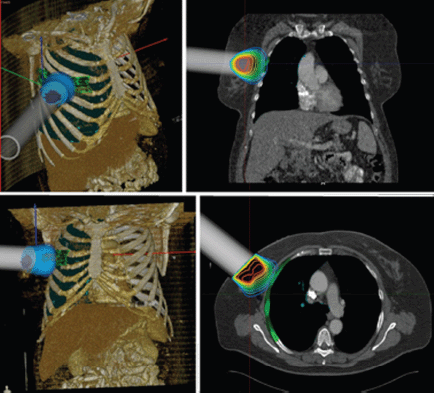

Intraoperative radiotherapy (IORT) is a procedure in which ionising radiation is administered during surgery. The technique involves the precise application of a high dose of radiation to the target volume area or region of interest, with minimal exposure to healthy tissue, which can be displaced and/or protected during the procedure (Figure 1) [1].

Figure 1: Technical description HGUGM IORT.

RADIANCE is the only tool designed and patented for IORT planning with US Food and Drug Administration approval and the European Community mark. Using a graphics engine, the system is capable of generating a three-dimensional image of the patient from a CT or MRI before surgery. Through segmentation on the axial, coronal, and sagittal planes, the user can generate a volumetric 3D image of organs at risk and the tumour bed. The system then determines the surgical field in real time and optimises the parameters of the applicator (cone diameter, bevel, energy, and dose). Finally, the platform allows optimisation of treatment parameters, by calculating a dose–volume histogram 4.7 (Figures 2–4).

Figure 3: IORT simulation using RADIANCE breast cancer.